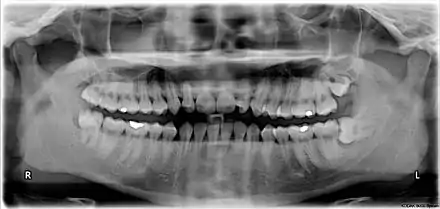

The upper left (picture right) and upper right (picture left) wisdom teeth are distoangularly impacted. The lower left wisdom tooth is horizontally impacted. The lower right wisdom tooth is vertically impacted (unidentifiable in orthopantomogram).